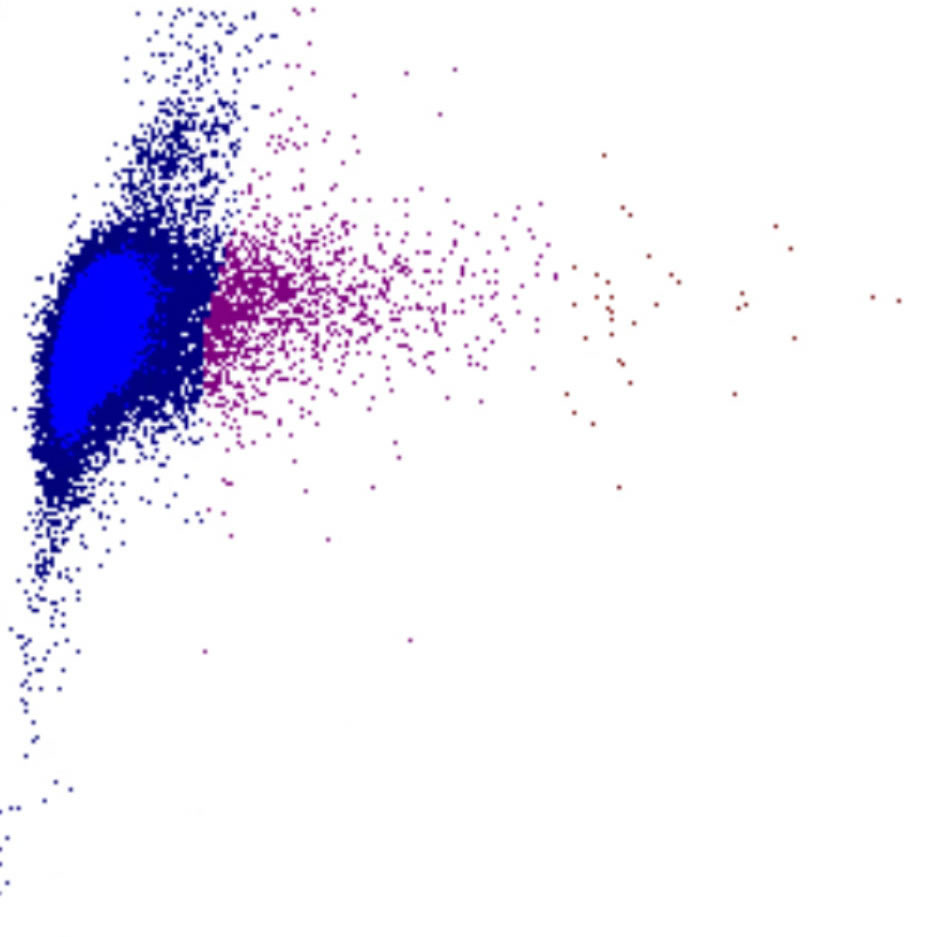

Selon les paramètres représentés l’un par rapport à l’autre, la combinaison de ces signaux détermine la position de chaque cellule sur le diagramme de dispersion. Cela génère des clusters caractéristiques pour les populations cellulaires normales et des motifs reconnaissables en cas d’anomalies.

Forward Scatter

Le FSC est une mesure de la taille cellulaire : des valeurs élevées de FSC indiquent des cellules plus grandes, tandis que des valeurs plus faibles correspondent à des cellules plus petites. Les plaquettes présentent le FSC le plus bas, tandis que les monocytes, les lymphocytes plasmocytoïdes et certains blastes figurent parmi les cellules les plus volumineuses.

FSC scatter

FSC faible

FSC élevé